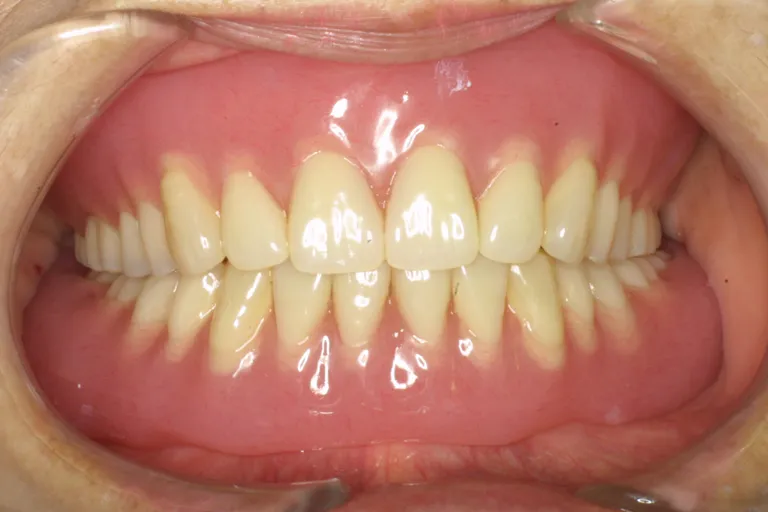

■術後の状態■インプラント・メタルボンド・アタッチメント義歯を含む包括的治療の例です

■術後の状態■

様々な治療法を

用いた

包括的治療の一例

■術後の状態■しっかりと噛める強度と快適な装着感で外からは自然な見た目です

しっかり噛める

口腔環境にします